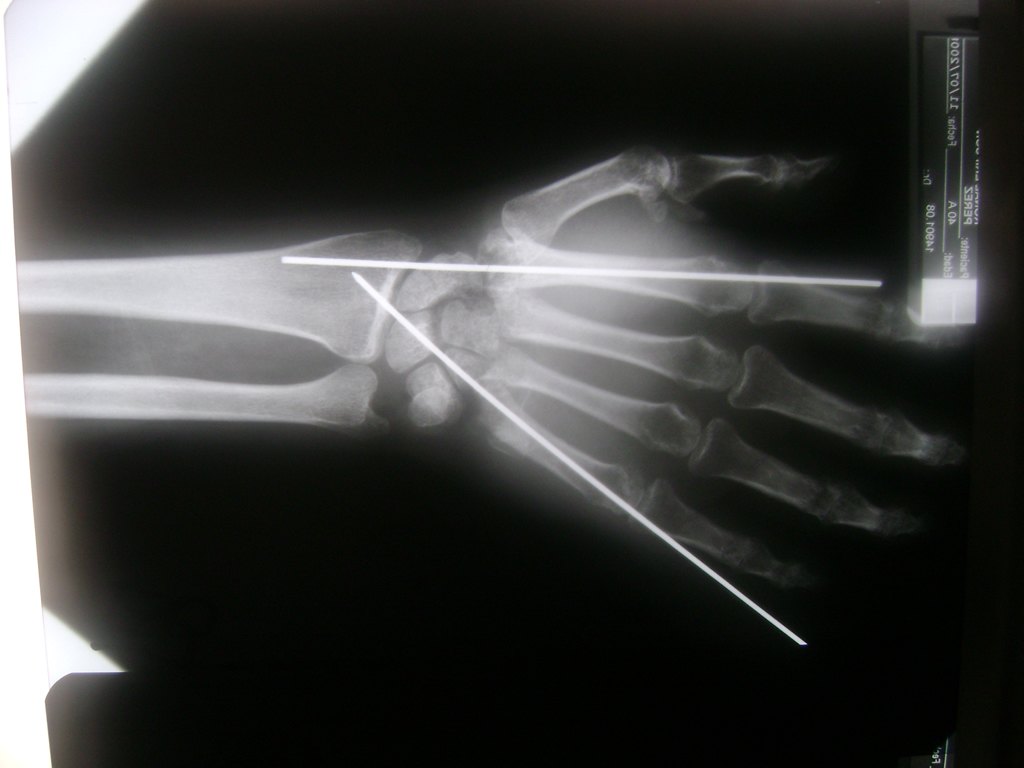

Cirugía de Muñeca y Mano

Los procedimientos más comunes en cirugía de la mano son aquellos destinados a reparar traumatismos, incluyendo lesiones de tendones, nervios, vasos sanguíneos, y articulaciones; huesos fracturados; y quemaduras, cortes, y otros daños de la piel.